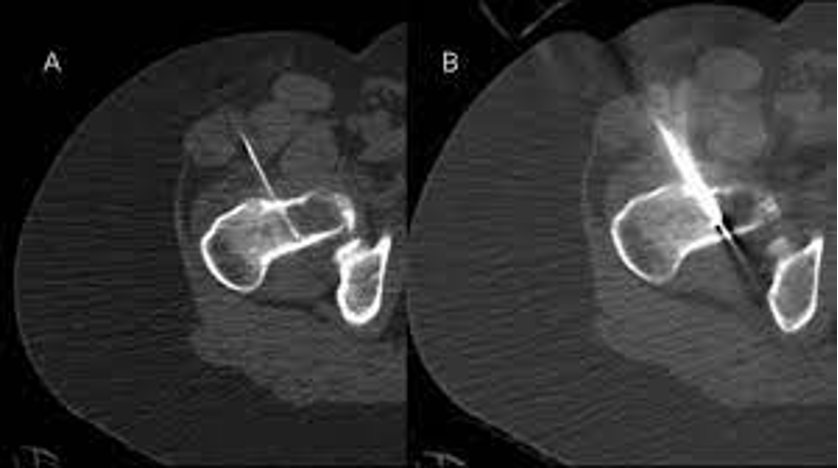

WorkupMetastatic Cancer to Bone

What does this refer to

Operative

Arthroplasty with adjuvant radiation

Spinal neurologic decompression/stabilization

+ post-op radiation

Indicated with mets to spine